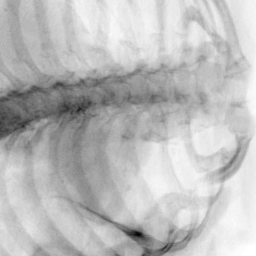

Exp. 3: Adult thorax data: To show the versatility of our approach we also apply it to adult thorax scans. For this experiment no organ specific training is performed but the whole volume is used. We evaluate reconstruction performance similar to Exp. 1 and Ti^^subscript𝑇𝑖\hat{T_{i}} prediction performance when ΩΩ\Omega is projected on an external plane, comparable to X-Ray examination using C-Arms. The latter provides insights about our method’s performance when applied to interventional settings in contrast to motion compensation problems. 60 healthy adult thorax scans were randomly selected, 51 scans used for ΩtrainsubscriptΩ𝑡𝑟𝑎𝑖𝑛\Omega_{train} and nine scans used for ΩvalidationsubscriptΩ𝑣𝑎𝑙𝑖𝑑𝑎𝑡𝑖𝑜𝑛\Omega_{validation}. Each scan is intensity normalised and resampled in a volume of 200×200×200200200200200\times 200\times 200 with spacing 1mm×1mm×1mm1𝑚𝑚1𝑚𝑚1𝑚𝑚1mm\times 1mm\times 1mm. Using the Fibonacci sampling method, 25 sampling plane of size 200×200200200200\times 200, evenly spaced between -50 and +50, were rotated over 500 normals. Training took approximately 20 hours for 60 epochs. Fig. 4c shows an example reconstruction result gaining 28dB PSNR with additional SVR. Ti^^subscript𝑇𝑖\hat{T_{i}} prediction takes approx. 20 ms/slice for this data.

Figure 4: (a): Comparison of a single slice from raw low-dose thorax CT data; (b): reconstruction based on SVRNet Ti^^subscript𝑇𝑖\hat{T_{i}} regression; (c): SVR initialized with SVRNet transformations after four iterations of SVR; (d): PSNR of (b) and (c) compared to (a). (e): shows a projection of an unseen pathological test CT volume as DRR and (e) shows a DRR at the location predicted by our method when presented with the image data in (e).

We use Siddon-Jacobs ray tracing [15] to generate Digitally Reconstructed Radiographs (DRRs) from the above described data. For training, we equally sample DRRs on equidistant half-spheres around 51 CT volumes at distances of 80cm, 60cm, and 40cm, between 90superscript90-90^{\circ} and 90superscript9090^{\circ} around all three co-ordinate axes. For validation, we generate 1000 DRRs with random rotation parameters within the bounds of the training data at 60cm distance from the volumetric iso-centre. We trained on healthy volunteer data and tested on nine healthy and ten randomly selected pathological volumes (eight lung cancer and two spinal pathologies). Our approach is able to predict DRR transformations relative to the trained reference co-ordinate system with an average translation error of 106mm and 5.6superscript5.65.6^{\circ} plane rotation for healthy patients, and 130mm and 7.0superscript7.07.0^{\circ} average error for pathological patients. An example is shown in Fig. 4e,f. Note that these values are good enough to robustly initialize intensity-based registration refinement. SVRNet prediction can be improved by generating a denser training data set, in particular, in more equidistant half-spheres.